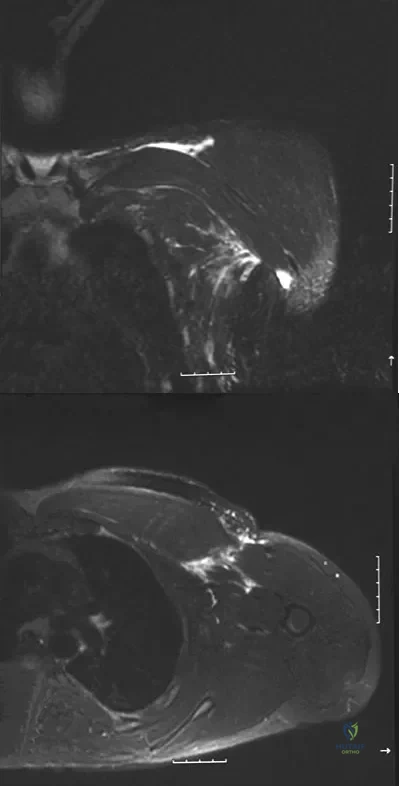

Question 47

A 38-year-old left hand-dominant bodybuilder reports ecchymosis in the left axilla and anterior brachium after sustaining an injury while bench pressing 3 weeks ago. Coronal and axial MRI scans are shown in Figures 16a and 16b. What treatment method yields the best long-term results?

Explanation